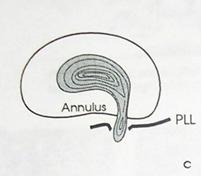

I стадия — протрузия диска — смещение в сторону позвоночного канала пульпозного ядра и выбухание в позвоночный канал элементов фиброзного кольца межпозвонкового диска без нарушения целостности последнего;

2 стадия — экструзия — выбухание в позвоночный канал элементов фиброзного кольца и дегенерированного пульпозного ядра;

— пролaпс — выпадение в позвоночный канал через дефекты фиброзного кольца фрагментов дегенерированного пульпозного ядра, сохраняющих связь с диском;